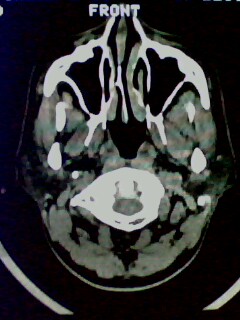

以下是引用随光逐影在2009-5-20 19:22:00的发言:[br]1)考虑左上颌骨近中线区含牙囊肿。2)鼻中隔右突偏曲。3)双侧下鼻甲肥大。